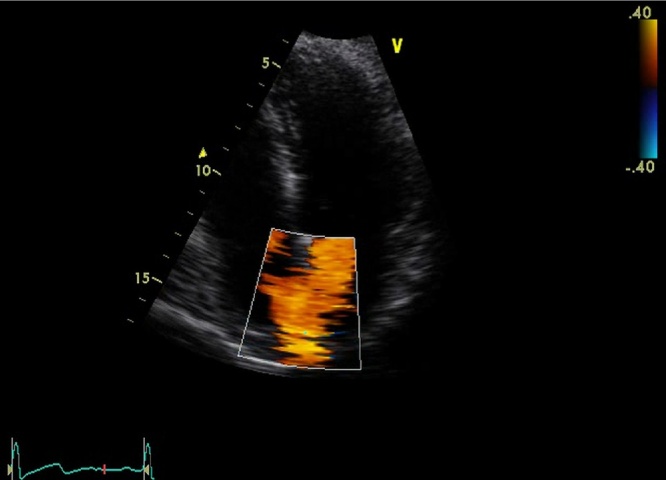

Fig. 2.

Colour flow echocardiogram reveals small jet via PFO.

A 50-year-old female presented with acute left-sided abdominal pain 9 days after laparoscopic sleeve gastrectomy for morbid obesity BMI 41. Her procedure was uncomplicated and she received standard deep vein thrombosis (DVT) prophylaxis which included peri-operative calf compressors, post-operative compression stockings (worn for the duration of hospital stay and given to the patient on discharge) and prophylactic dose of 40 mg enoxaparin daily commenced on the day of surgery and continued during inpatient stay (3 days total). She had no significant medical history, normal postoperative recovery and was discharged home on day two. She was walking on treadmill on day 9 when she developed the pain. On examination blood pressure 140/80 mmHg, heart rate 68 bpm, respiratory rate 17/min, saturation 98%, temperature of 36C with localised left-sided and epigastric tenderness and no peritonism. Pathology showed WCC 5.5 × 109/L, Hb 130 g/L, CRP 6 mg/L with normal liver and renal function. CT of abdomen and pelvis revealed an anterior-inferior left renal wedge infarction and incidental bilateral renal and hepatic cysts (Fig. 1). Renal Doppler showed normal arterial and venous flow without evidence of renal thrombus. ECG has revealed sinus rhythm and a 24-h Holter monitor showed sinus rhythm with rare ventricular ectopic beats. Thrombophilia screen (coagulation profile, ESR, protein-C, protein-S, antithrombin-III, nuclear and cardiolipin antibodies) was normal. Factor VIII was mildly elevated at 235% (normal high range 220%) but not clinically significant. Bilateral lower and upper limb Doppler ultrasound showed good flow in deep venous system and no thromboembolism. Transthoracic echocardiogram (TTE) showed good contractility and no evidence of thrombus or valvular disease. Colour flow echocardiogram revealed left-to-right jet. Qp:Qs was 1.25 indicating a small shunt through patent foramen ovale (Fig. 2). She was discharged home on warfarin (target INR 2–3) with minimum duration of therapy of 6 months and was assessed by a cardiologist as an outpatient for the ongoing management of PFO.